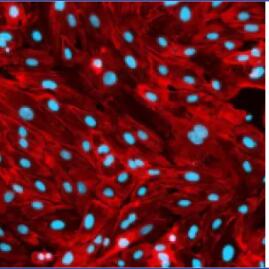

8、血管化3D生物模型,具有器官基质的分化内皮的生理维持>5天

标准多孔板上的血管化免疫活性类器官

> 血管化免疫功能模型

获得专利的微流体多孔技术允许通过内皮将孔与循环药物和免疫活性细胞互连

微孔的粘合底面4DCell技术将均匀的球体固定在透明水凝胶中,与实时成像完兼容。结合 Cherry Biotech 的微流体灌注技术,

通过施加恒定的剪切应力来区分内皮层,在球体顶部创建无膜功能性血管界面 。这些组合技术可以特地将您的球体保存在带有培养基(支持持续营养供应)

的单个孔中数周,并允许。这些组合技术可以以特的方式在几周内在 24 孔板上并行观察多达 2000 个球体。实时成像您的药物或免疫活性疗法的效果